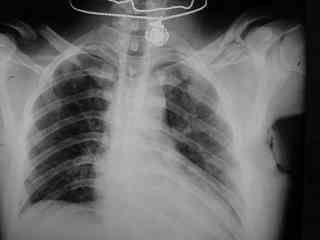

Bolnogo operirovali plastinami, snimky zdes'.

CIMG1145.JPG

Похоже, все прошло по плану. Поздравляю с успешной операцией!

Pneumatorax hirurg punctiroval i lechil dalshe, operasia zanimala 1 chas 35 minut, ni bilo problem ossobih.